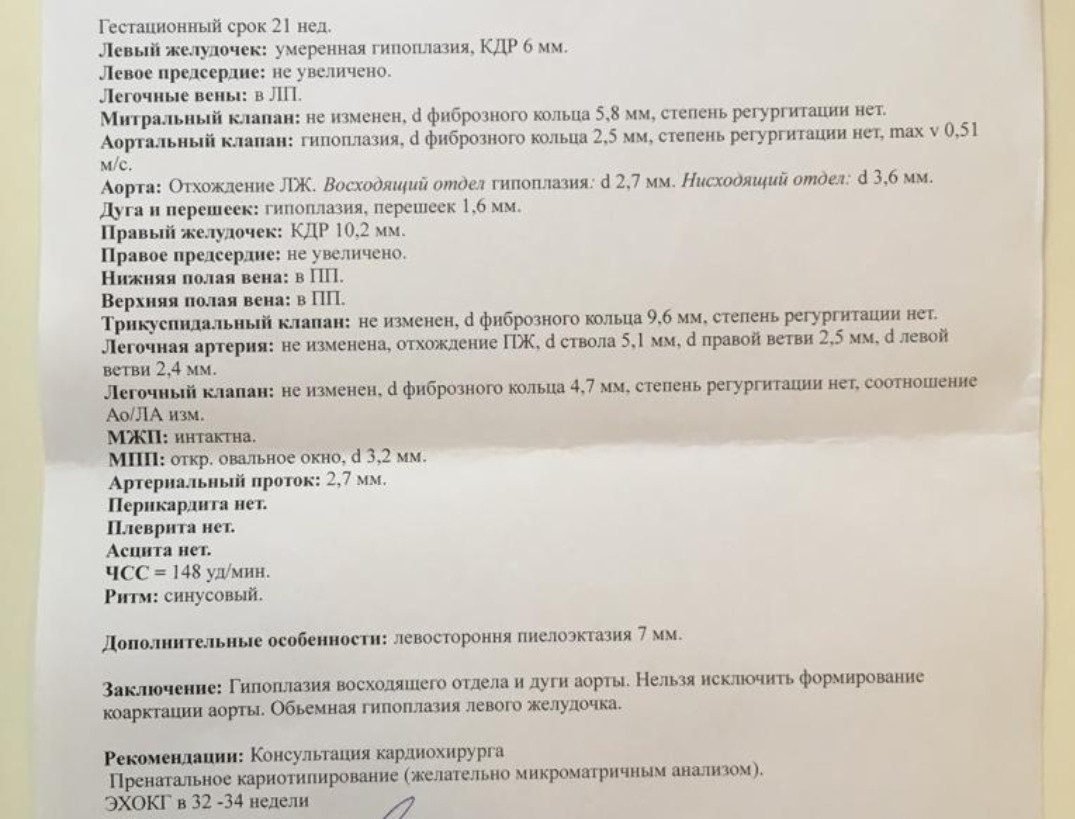

Нормальный диаметр корня аорты: медицинские нормы и отклонения